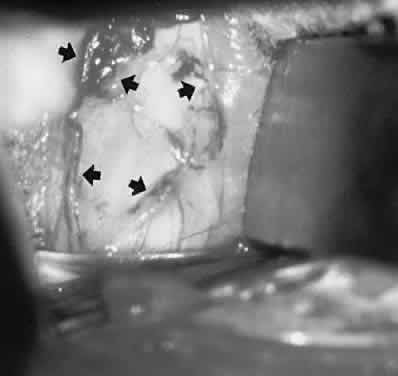

Fig. 23. Exposure of supraorbital vein (arrows) for endovascular interventional closure of cavernous sinus fistula.

In patients with unsuccessful transarterial embolization of cavernous-dural fistulas, a medial lid crease or a sub-brow incision can be used to locate the dilated anterior superior ophthalmic vein for transvenous embolization (Fig. 23; see also Volume 2, Chapter 17, Fig. 21C). Sharp dissection is carried superiorly in the preseptal plane until the arcus marginalis is reached. The orbital septum is incised along the width of the skin incision. The trochlea and superior oblique tendon are identified and insulated with neurosurgical cottonoids. The orbital fat adjacent to the trochlea is moved laterally with a pair of malleable retractors. Orbital fat septa are bluntly dissected apart to prolapse the superior ophthalmic vein forward. Once identified, the vessel is insulated with ½-inch neurosurgical cottonoids to prevent herniating fat from obscuring the surgical field. Two 2-0 silk ligatures are placed around the vein for traction. A guidewire is introduced through a venipuncture between the two ligatures. An angiographic catheter is threaded over the guidewire and secured to the vessel with a silk suture. With successful closure of the shunt, the vessel is no longer arterialized. The silk ligatures are then loosened and the venipuncture site cauterized with a bipolar cautery.